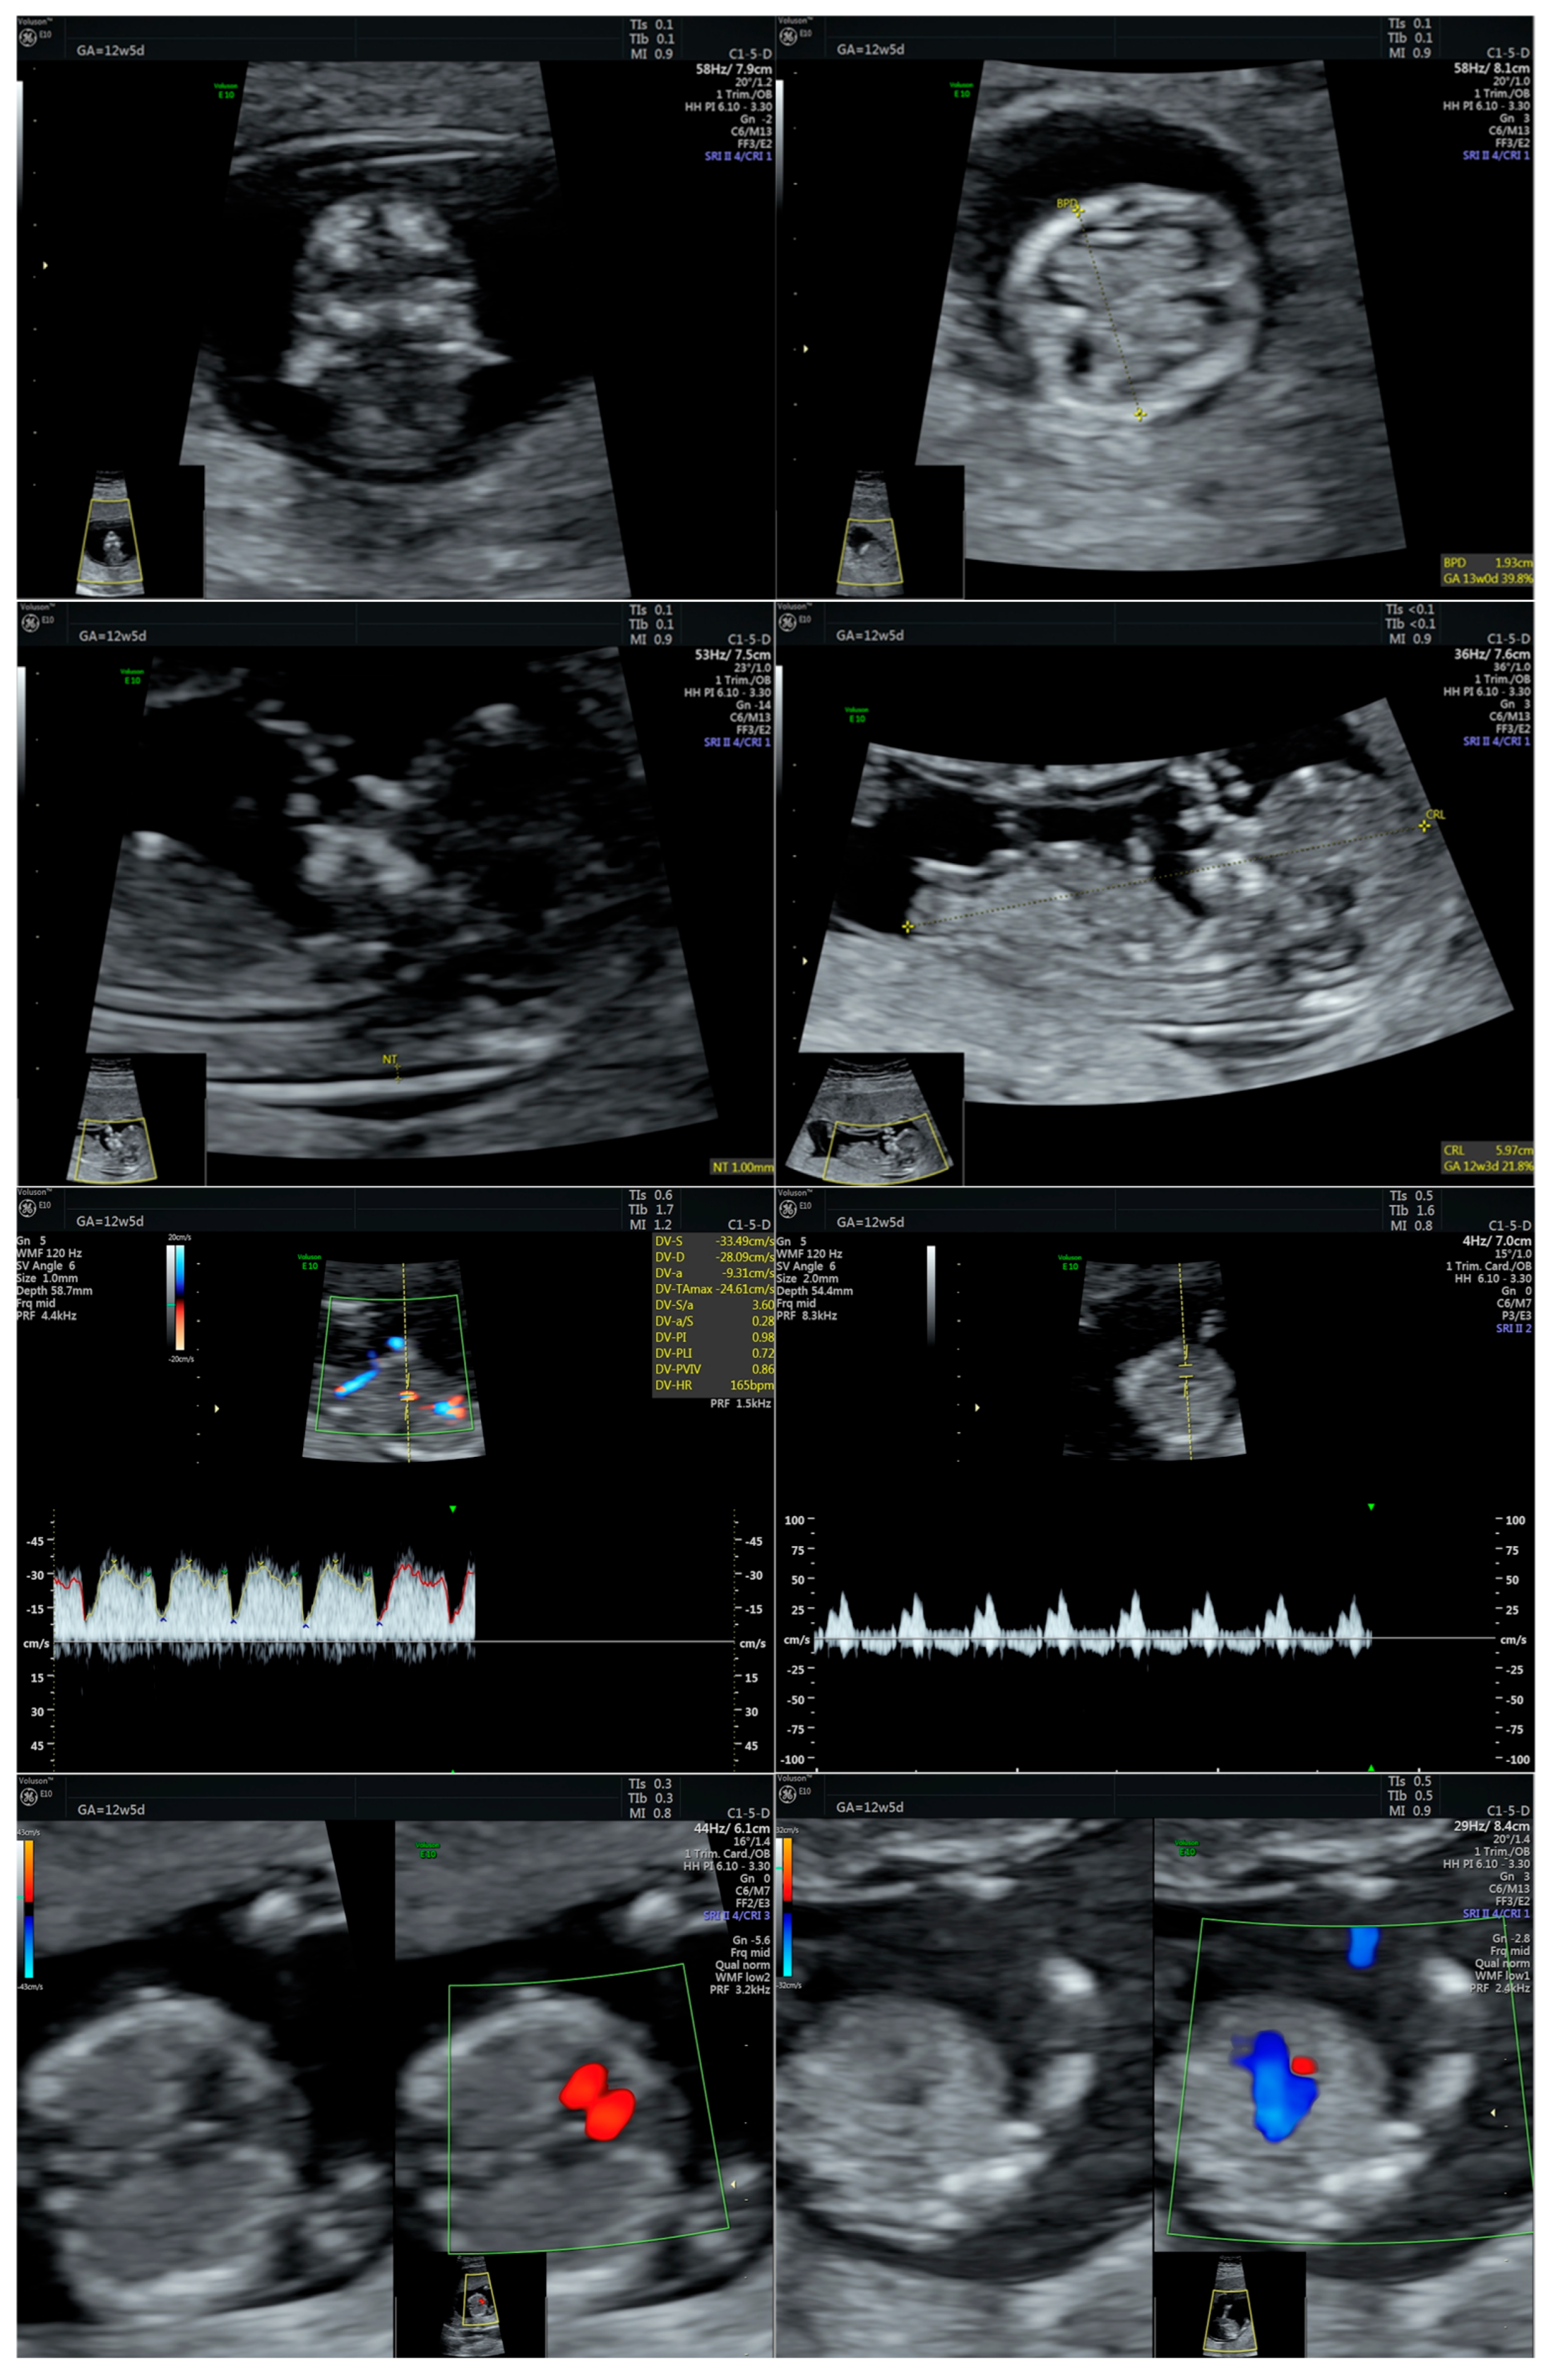

2.1. Case Presentation

2.2. Case Management